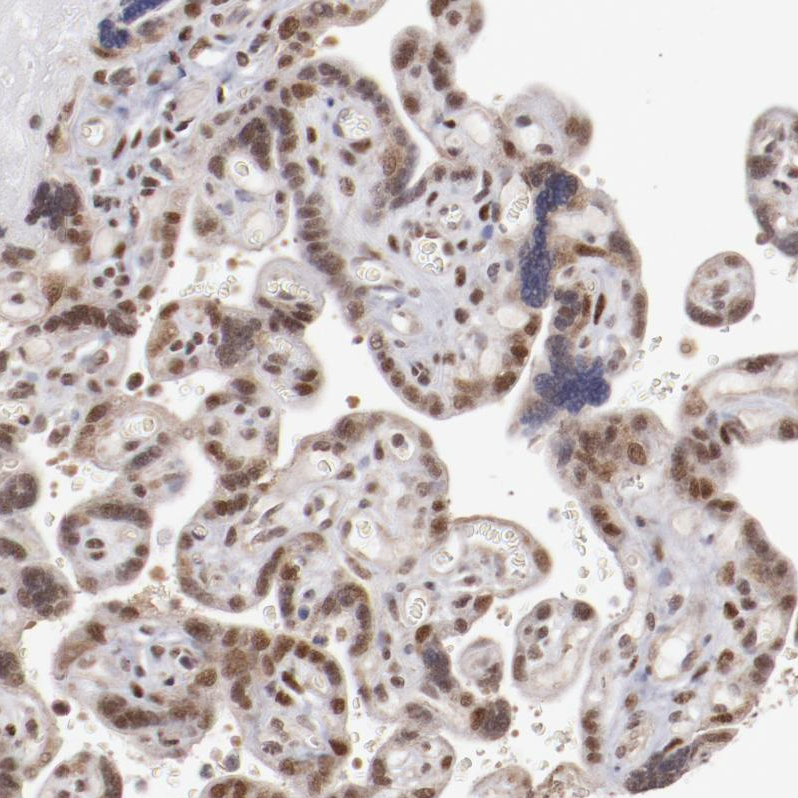

Immunohistochemical staining of human placenta shows strong nuclear positivity in trophoblastic cells.